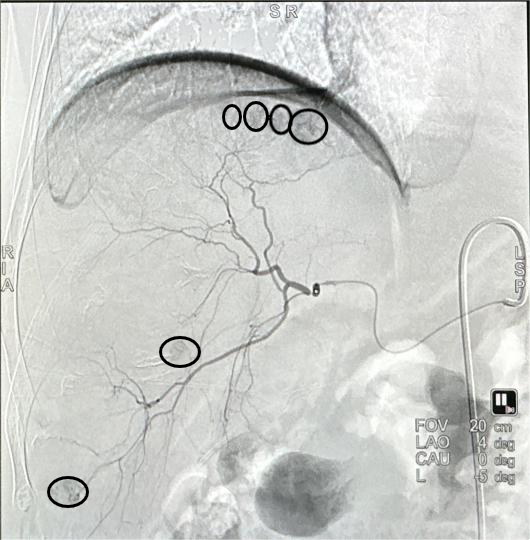

一切准备就绪,放射科主任罗谞成协助朱晖教授进行介入手术。穿刺点局麻后,朱晖教授在B超引导下穿刺插管,在DSA设备的帮助下,对肝右及肝中动脉较纤细、远段分支位置的六处结节进行精准打击。术中,朱晖教授把导管送进肝肿瘤的供血动脉中对其进行栓塞,阻断其血供,使肿瘤趋于坏死,并向病灶集中释放药物。手术非常顺利,历时仅2小时。由于患者血小板较低,为防止血肿的发生,朱晖教授亲自按压止血30分钟,确定穿刺处无出血、无血肿后,再进行加压包扎。最后安全护送患者至病房,并进行了详细的术后指导。患者及家属不胜感激:“这趟求医之路实在是太值得了,朱教授又救了我一命,谢谢你们!”这是患者的肺腑之言,也是医患间最动人的情谊。

术前造影——多发肿瘤